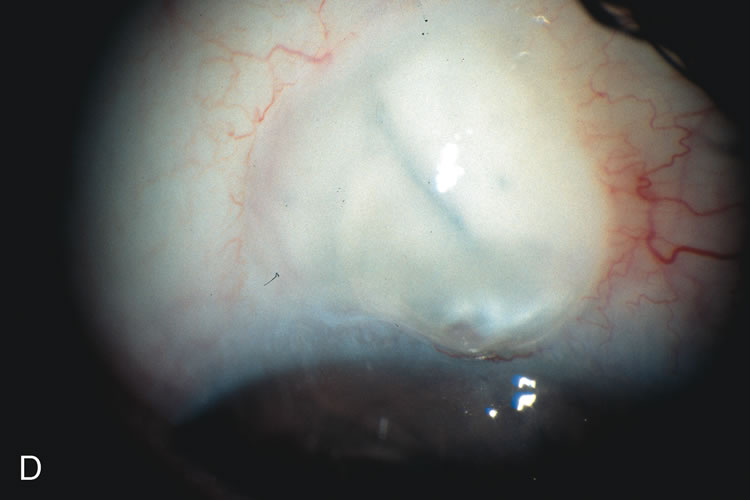

Fig. 8. Bleb appearance after limbus-based versus fornix-based conjunctival flaps. Even though the IOP is thought to be equivalent between limbus and fornix-based conjunctival flaps, the final bleb appearance varies considerably. A. During a limbus-based approach, an incision through conjunctiva 10 mm posterior to limbus will sever through multiple arterial vessels, increasing the likelihood of an avascular bleb. B. The tissues are dissected down to the sclera further cutting feeder vessels from Tenon's capsule. C. The wound is closed inciting a cascade of wound healing events that may ultimately lead to scarring producing a barrier to aqueous flow. D. This leads to walling off of a bleb that has lost some of its overlying vascularity (pale cystic avascular bleb). E. During a fornix-based conjunctival approach, the incision is made at the limbus and tissues undermined. F. The incision is closed at the limbus; no conjunctival vessels are severed over the bleb area. G. This fosters the formation of a shallow diffuse pale bleb with a normal vessel pattern.